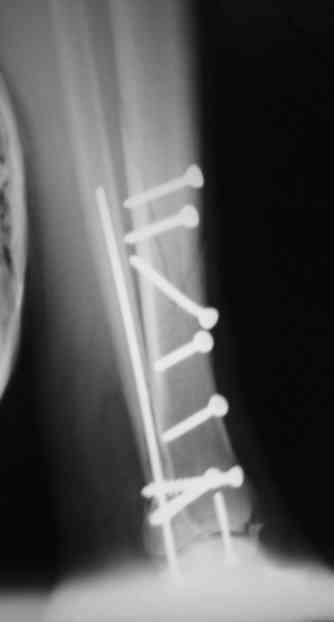

Во вложении - картинки из моей книжки как раз по этой теме

Схемы коррекции различных видов смещения в аппарате

Коррекция длины

Коррекция ротации

Коррекция ширины

В следующих письмах - дополнительные иллюстрации

Открытая репозиция.

Ничто особо не мешает, наоборот - все видно, требования к фиксации не очень высоки - можно просто фиксировать спицей или винтомю Внешний аппарат берет основную нагрузку